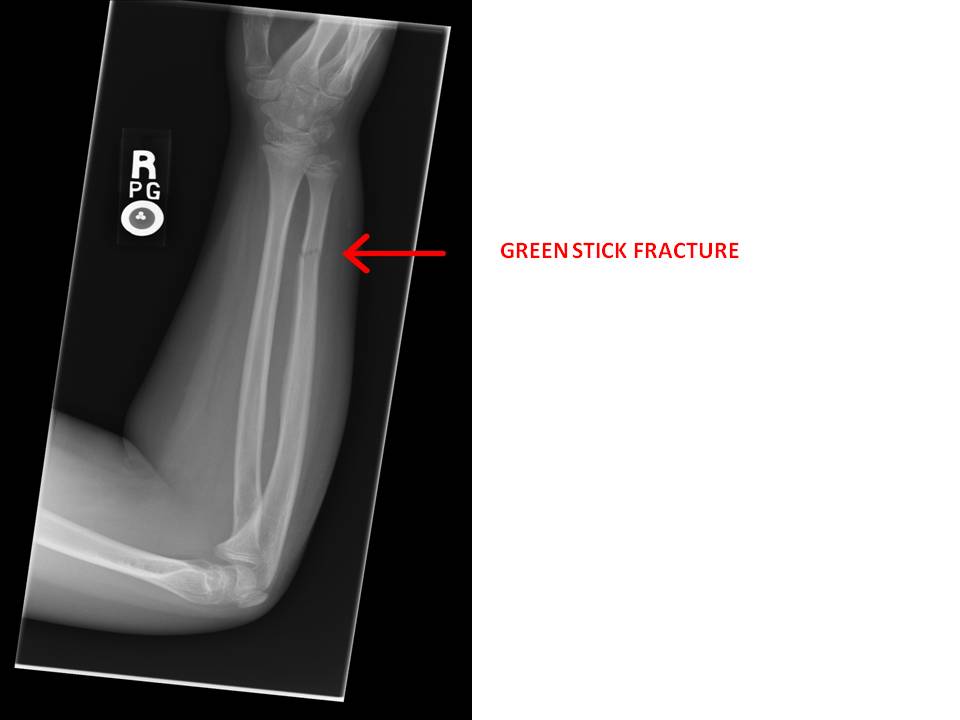

- Too much rigorous rubbing has led to “green stick fractures” in the baby. A green stick fracture is a fracture in a young, soft bone in which the bone bends and breaks. Despite the name “fracture”, during the majority of cases the bone is broken and hard to find in x-rays.